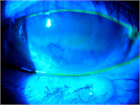

1. 多量の眼脂、眼痛、視野障害、毛様充血はred flag signであり、緊急で治療が必要になることがあり、眼科に早急にコンサルトすることが推奨される(推奨度1)

1. 感染性眼疾患は治療が遅れると、感染リスクを増加させたり、角膜穿孔を引き起こしたりして失明に至る可能性があり、疑われた場合には早急に眼科受診を勧める(推奨度1)